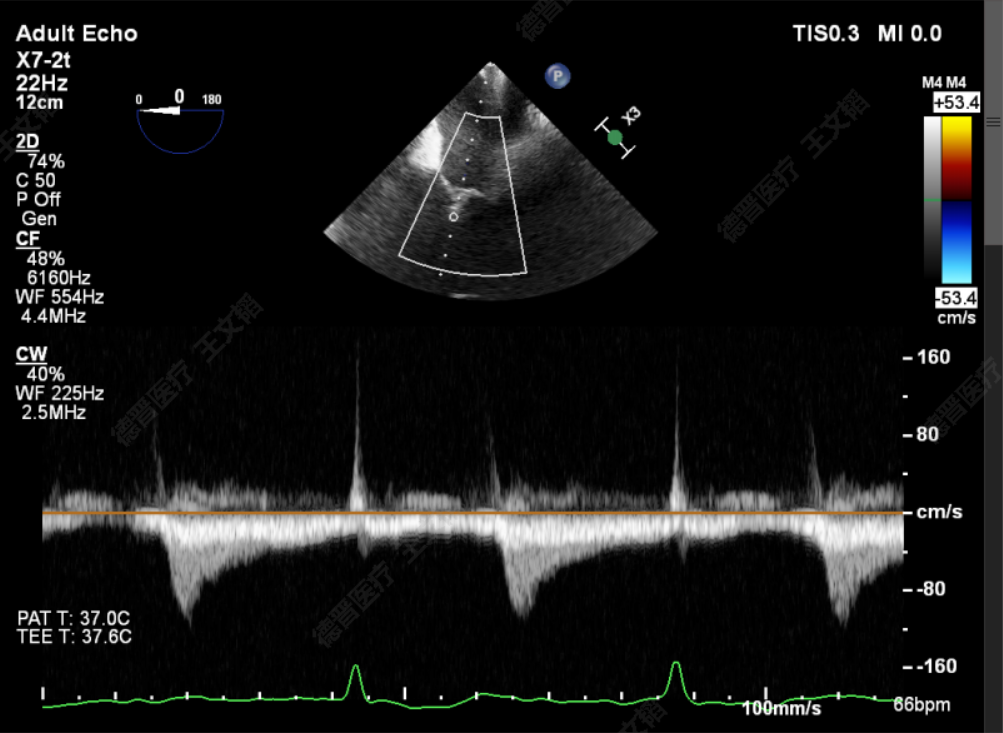

术中

TTE上彩评估无明显反流

L侧残余微量功能性反流

TMPG:1mmHg

肺静脉逆流消失